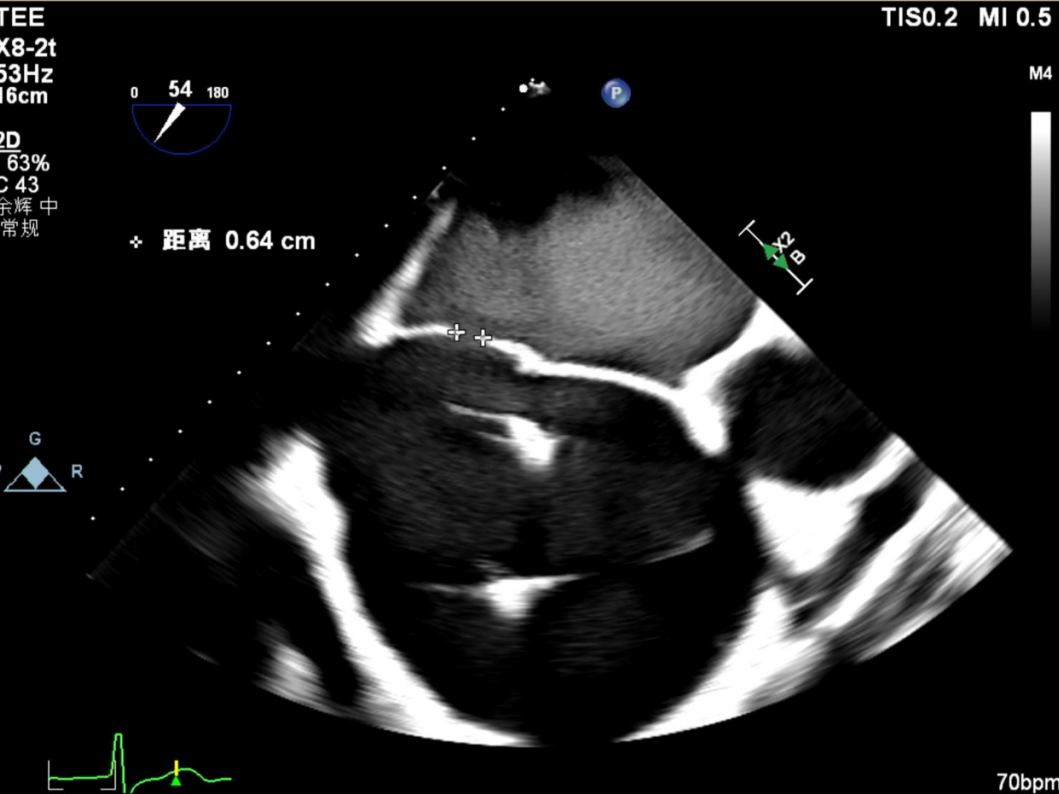

撤出大鞘后,患者出现低氧血症。经食道超声上下腔切面可见房间隔穿刺处存在右向左分流。观察期间患者氧合难以维持,考虑与极重度三尖瓣反流和医源性房间隔缺损(宽度约6.4 mm)有关。遂于该房间隔缺损处植入上海记忆合金封堵器(ASD 24),术后患者低氧血症明显改善,手术顺利结束。

怎么上穿刺鞘攻克巨大左房伴转位穿刺难关!温医大附一院周浩教授团队创新应用“导丝定位+可调弯鞘”技术完成高难度TEER手术_https://www.jmylbn.com_新闻资讯_第42张

大鞘撤离后右向左分流

怎么上穿刺鞘攻克巨大左房伴转位穿刺难关!温医大附一院周浩教授团队创新应用“导丝定位+可调弯鞘”技术完成高难度TEER手术_https://www.jmylbn.com_新闻资讯_第43张

术后残留房缺宽度6.4mm